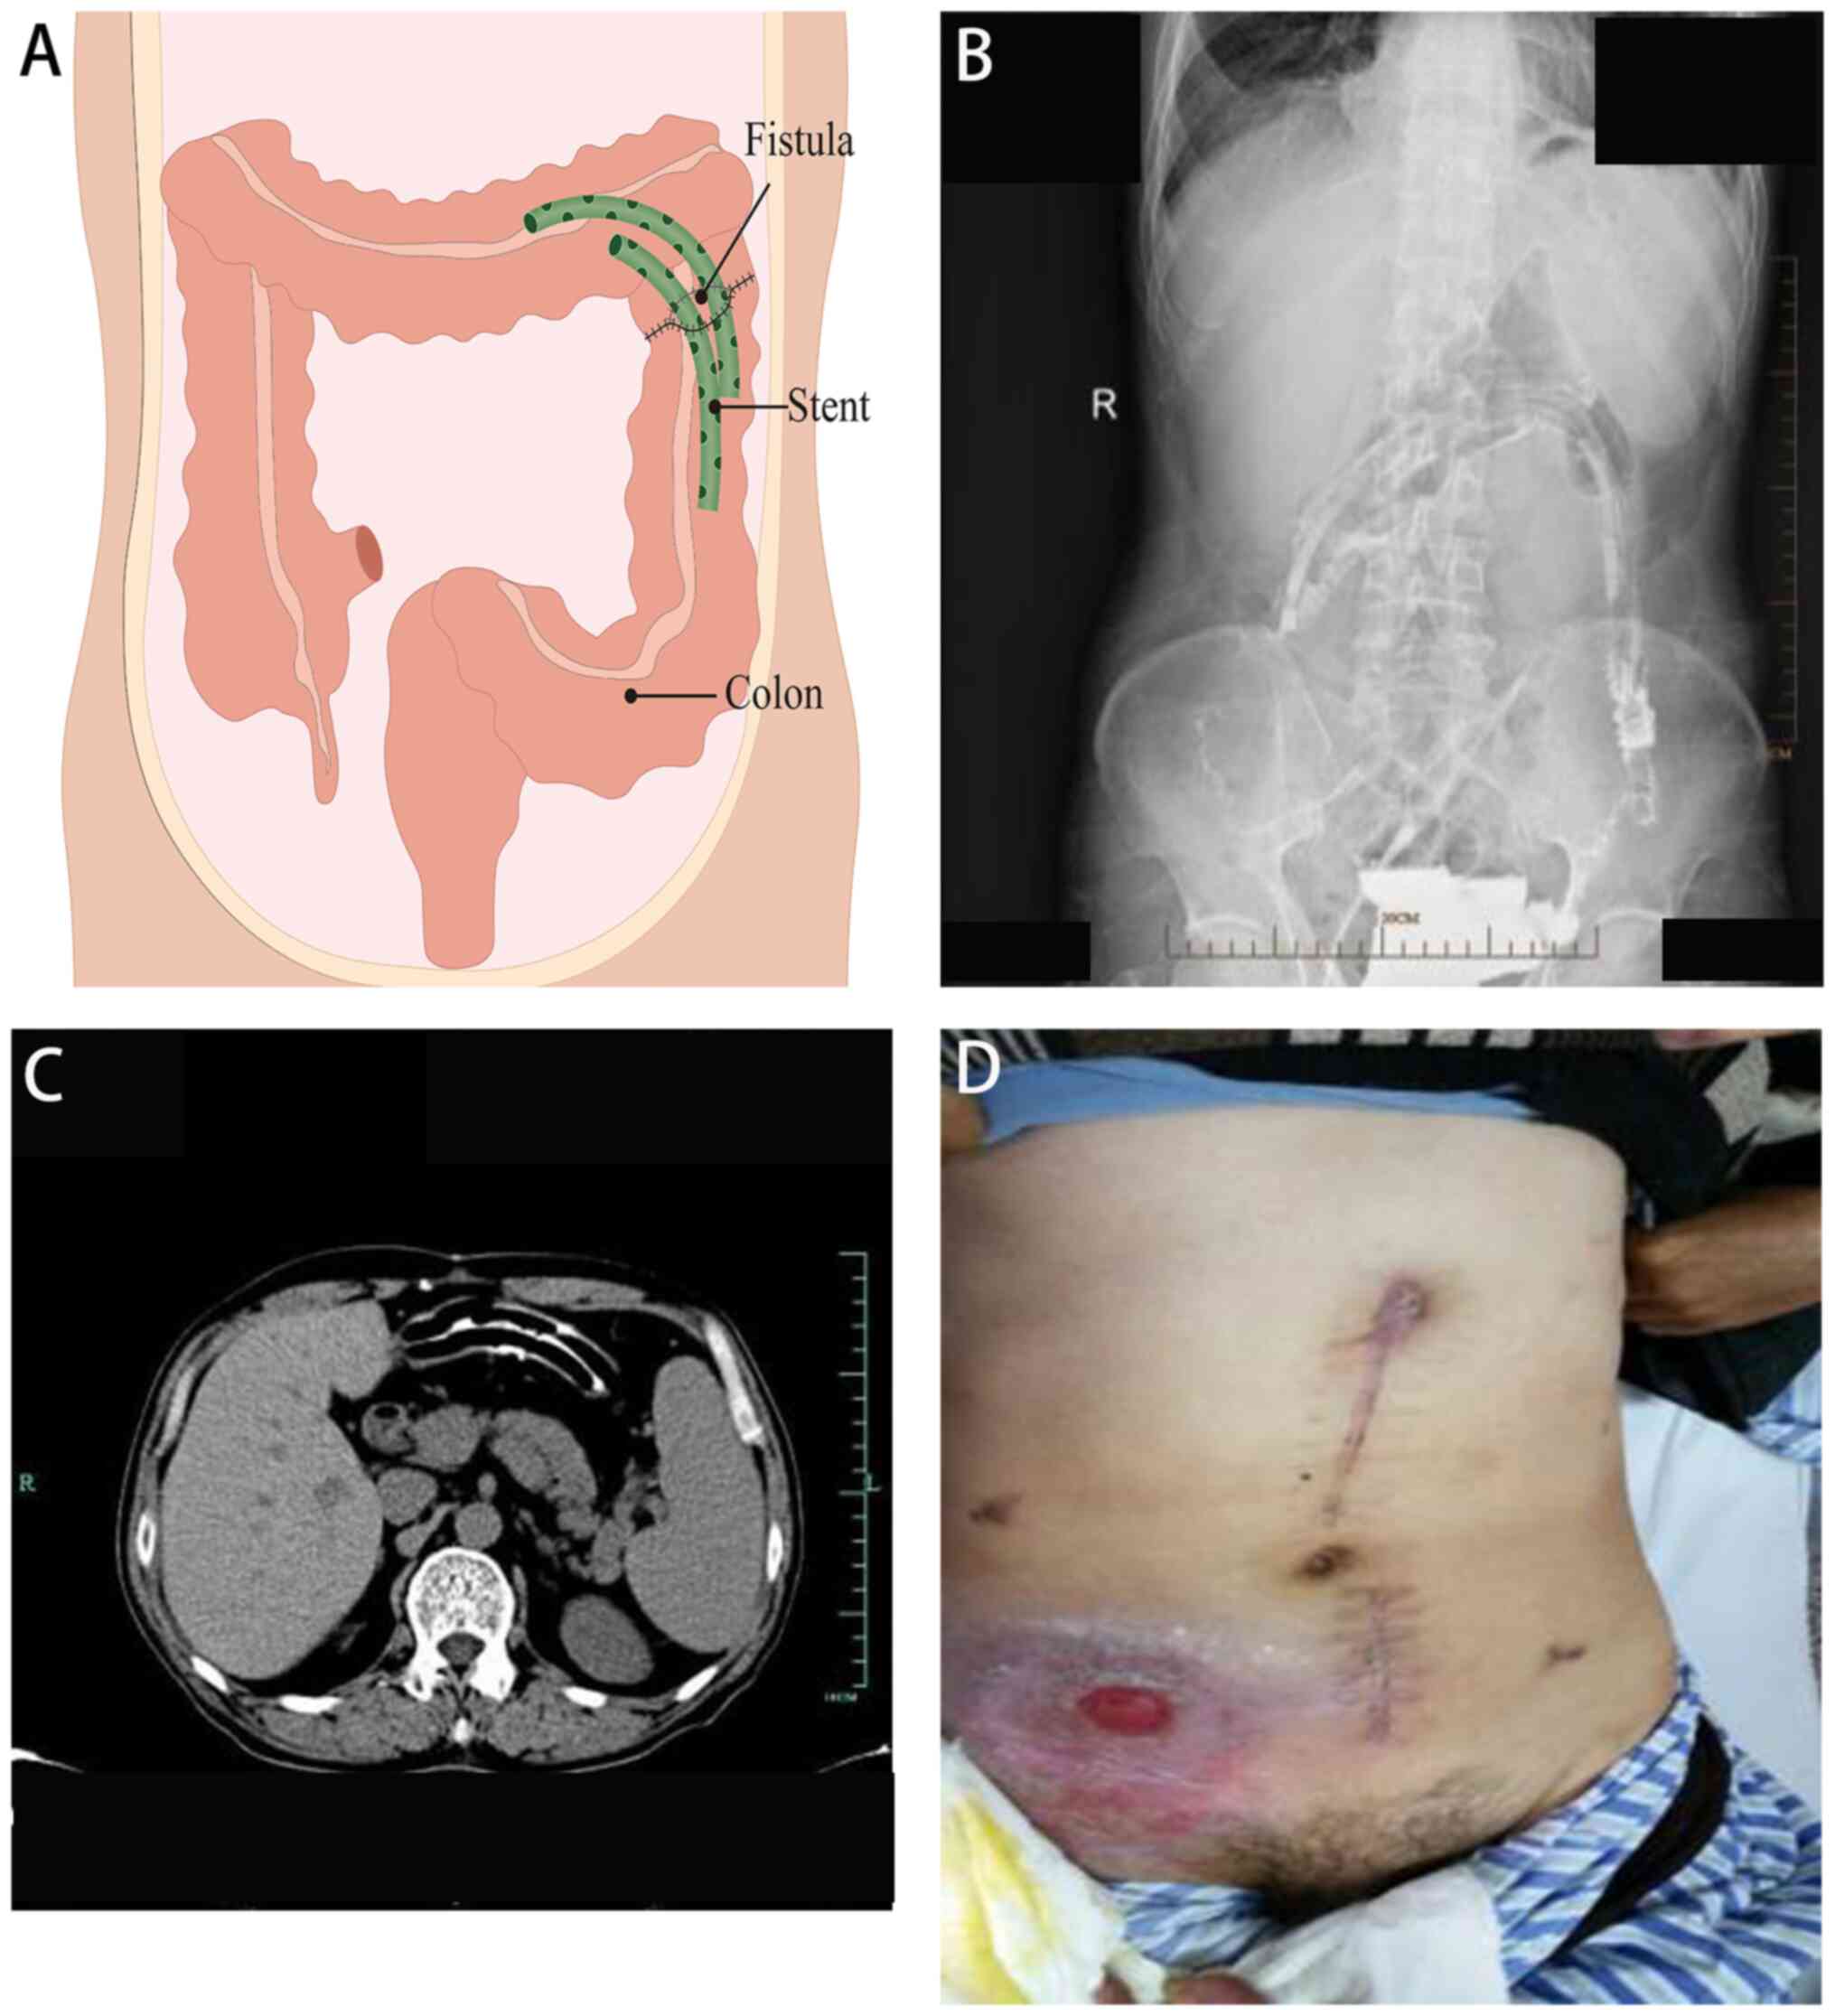

The third stage of treatment involved the insertion of drainage stents into the colon (6-10 weeks after admission). Two colon drainage tubes, each measuring 12 cm in length, were utilized. Multiple side holes were cut along the tubes, which were then bound together and fully inserted into the colonic cavity. To prevent stent displacement due to intestinal peristalsis, they were suspended and secured in place using 10# silk thread at the midpoint. A total of 8 weeks after admission, a small amount of leakage was observed at the incision site on the upper abdomen, and the fixed thread was removed. A total of 10 weeks after admission, skin leakage in the upper abdominal colon completely healed (Fig. 3).

Figure 3

Insertion of drainage stents into the colon. (A) Illustrative image. (B) Radiographic examination. (C) Computed tomography examination. (D) Skin fistula healing.